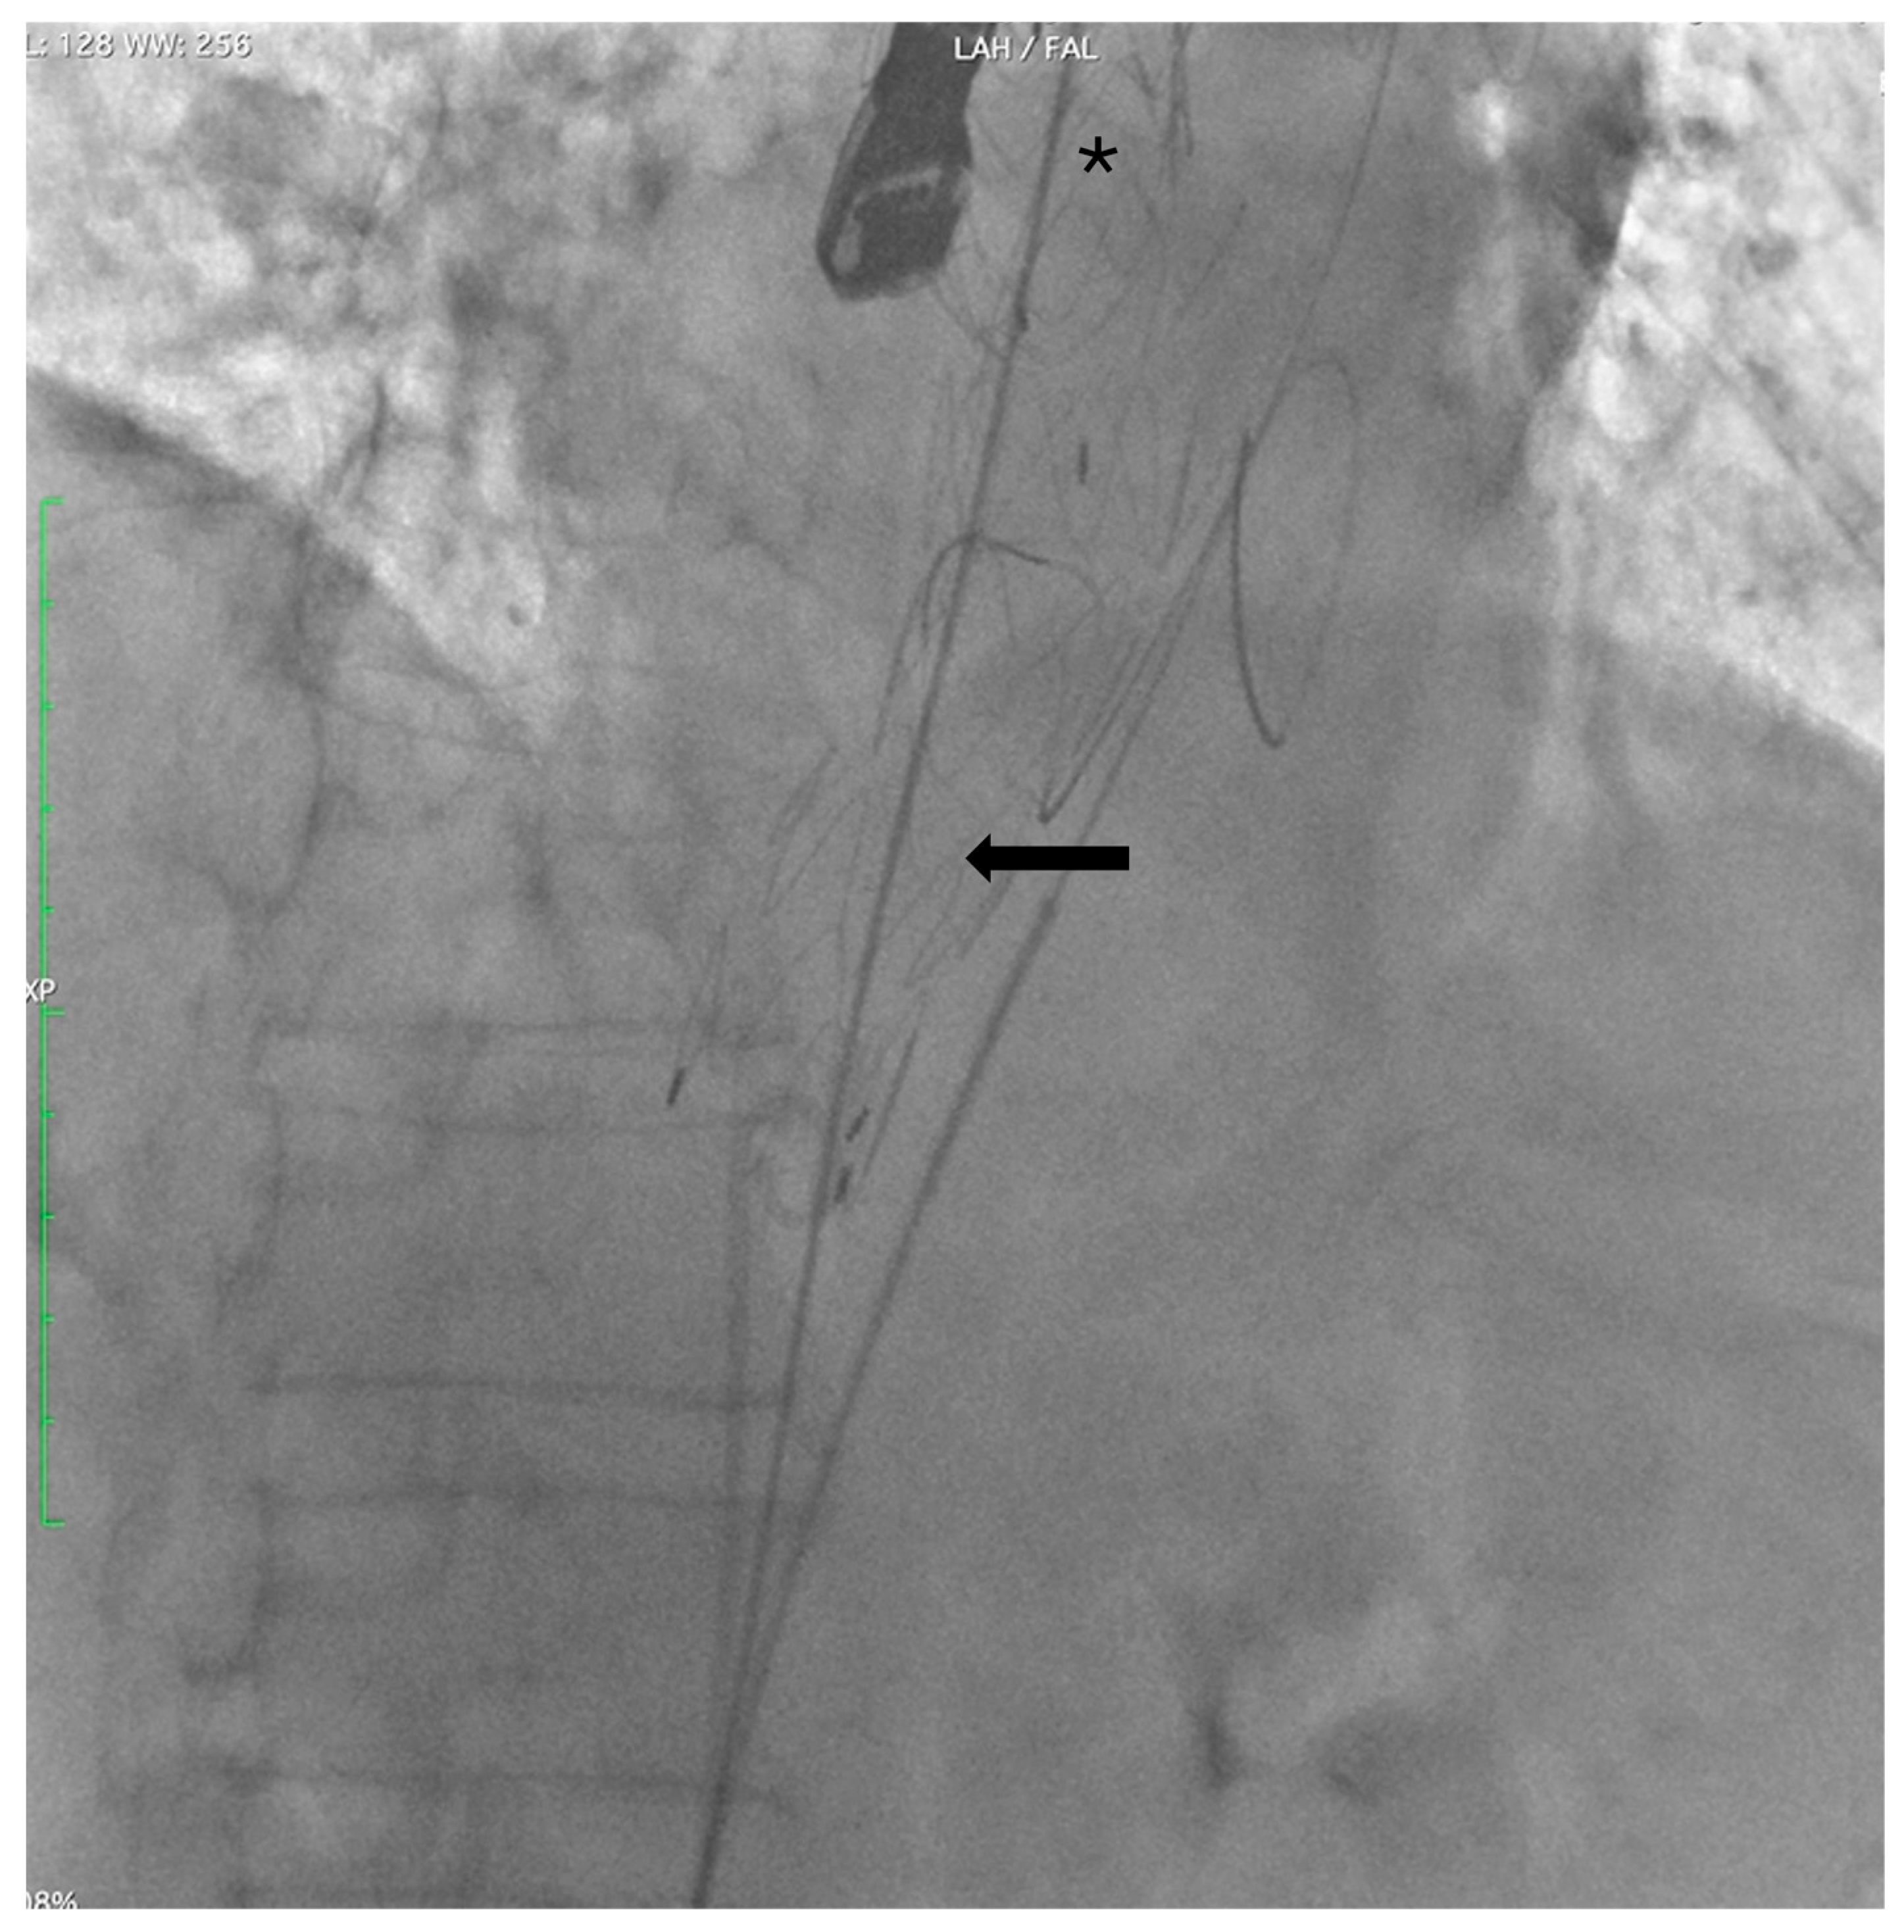

Two extra-stiff guidewires were positioned: one via the RCFA into the true lumen (TL), and the other via the LCFA into the FL. A Terumo Aortic endograft (36–32–199 mm) was deployed over the RCFA guidewire with partial overlap of the existing stent graft, successfully sealing the distal re-entry tears. (Figure 3).

Figure 3.

Angiographic control after deployment of a Terumo Aortic endograft (arrow) into the true lumen, partially overlapping the prior TEVAR (*).